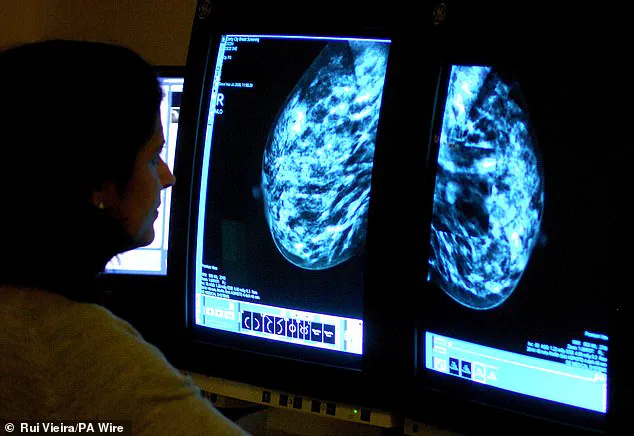

The surgeon also addressed the role of breast density in detection, a factor that has gained increasing attention in recent years.

Dense breast tissue, which is common and normal, makes breast cancer harder to detect on mammograms. 'Ask if your breast density is noted on your mammogram,' Dr.

Ramsey urged, noting that additional imaging may be required for women with dense tissue.

Research has shown that dense breast tissue is a significant risk factor, with over a million women in the UK alone estimated to be at heightened risk due to this characteristic.

Density, she noted, is not something that can be felt or spotted without a mammogram, making regular screening even more critical.

Dense breast tissue, characterized by a higher proportion of fibrous and glandular tissue compared to fatty tissue, is a well-known challenge in mammography.

It can obscure small tumors, making them harder to detect.

Experts are increasingly calling for a shift in policy, urging that women be notified of their breast density and offered supplementary imaging, such as ultrasound or MRI, which may provide clearer results.